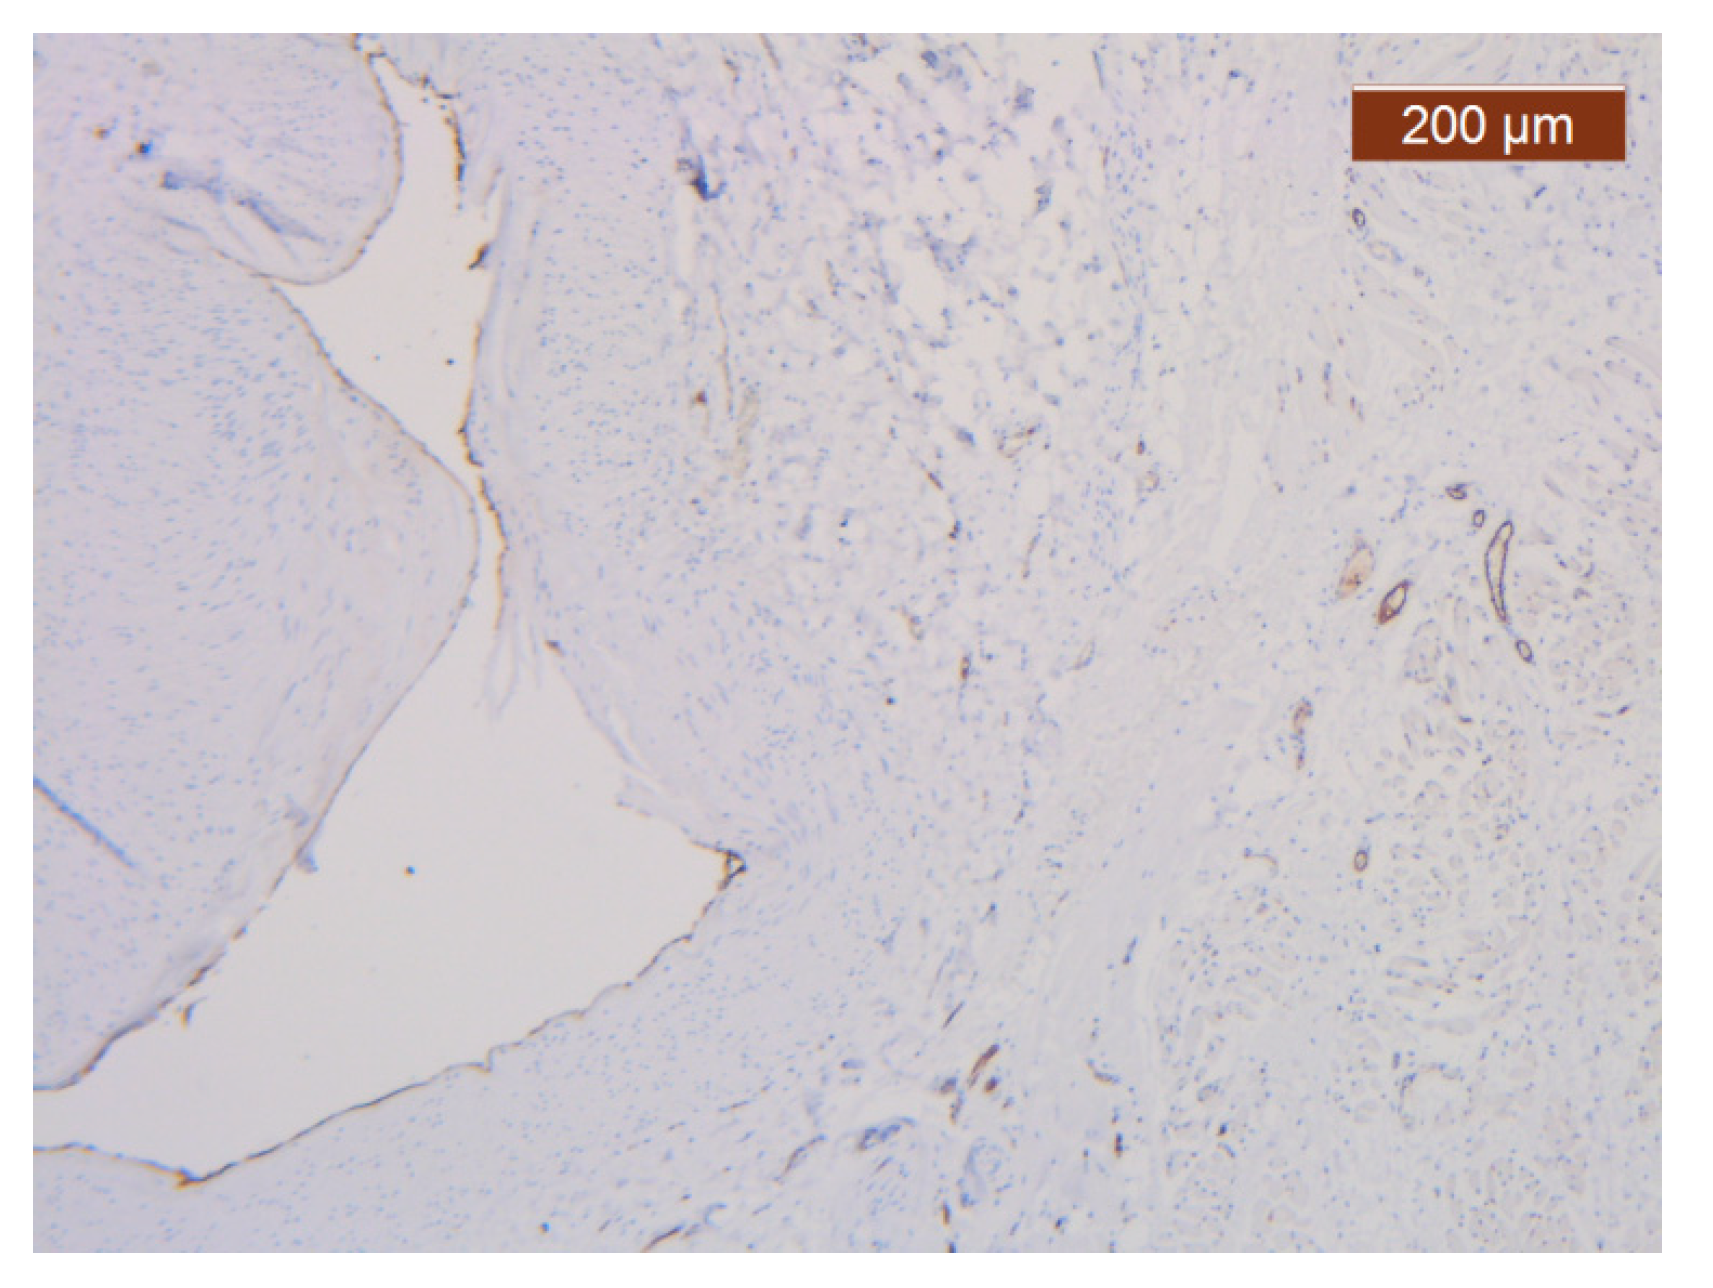

Figure 21. ICAM-2 staining was negative except in blood vessel walls (anti-ICAM-2 ×10 (left), 5 (right)). Staining intensity: weak to moderate.

The region of the nose located medial to the nasolabial fold also presented distinct characteristics at the level of the SMAS bed. The collagen fibers had the densest appearance among the explored regions (Figure 18). This three-dimensional collagen network is distributed toward the superficial dermis and also descends into the deep dermis. At this level, it delimits and seals the large blood vessels (Figure 18, Figure 19 and Figure 20).

With the exception of the walls of the large blood vessel captured on the dissected specimen, the expression of the endothelial marker was zero. It is likely that the nutrition of tissues at this level is achieved by microperfusion from the neighboring regions. (Figure 21).